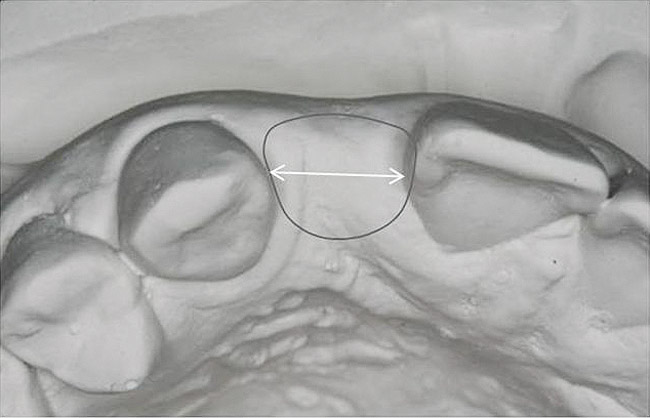

Figure 13   Exploiting study casts for planning single-tooth implant placement and restoration: Mounted study casts permit an estimation of available bone volume (Fig 13); measure the bound edentulous space inter-tooth dimensions (Fig 14); measure the available inter-arch dimension (restorative space) (Fig 15); and evaluate alveolar ridge/tooth relationships (distance from zenith represented by plastic stent to ridge crest) (Fig 16).

Figure 14   Exploiting study casts for planning single-tooth implant placement and restoration: Mounted study casts permit an estimation of available bone volume (Fig 13); measure the bound edentulous space inter-tooth dimensions (Fig 14); measure the available inter-arch dimension (restorative space) (Fig 15); and evaluate alveolar ridge/tooth relationships (distance from zenith represented by plastic stent to ridge crest) (Fig 16).

Figure 15  Exploiting study casts for planning single-tooth implant placement and restoration: Mounted study casts permit an estimation of available bone volume (Fig 13); measure the bound edentulous space inter-tooth dimensions (Fig 14); measure the available inter-arch dimension (restorative space) (Fig 15); and evaluate alveolar ridge/tooth relationships (distance from zenith represented by plastic stent to ridge crest) (Fig 16).

Figure 16  Exploiting study casts for planning single-tooth implant placement and restoration: Mounted study casts permit an estimation of available bone volume (Fig 13); measure the bound edentulous space inter-tooth dimensions (Fig 14); measure the available inter-arch dimension (restorative space) (Fig 15); and evaluate alveolar ridge/tooth relationships (distance from zenith represented by plastic stent to ridge crest) (Fig 16).